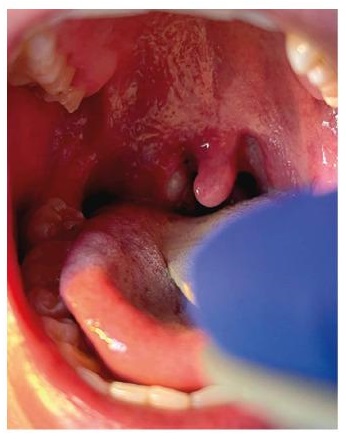

Right tonsillar enlargement with an overlying pustular lesion and yellow-green exudate with slight deviation of the uvula

BMJ. 2022 Jul 28;378:e072410; CC-BY-NC 4.0 licence